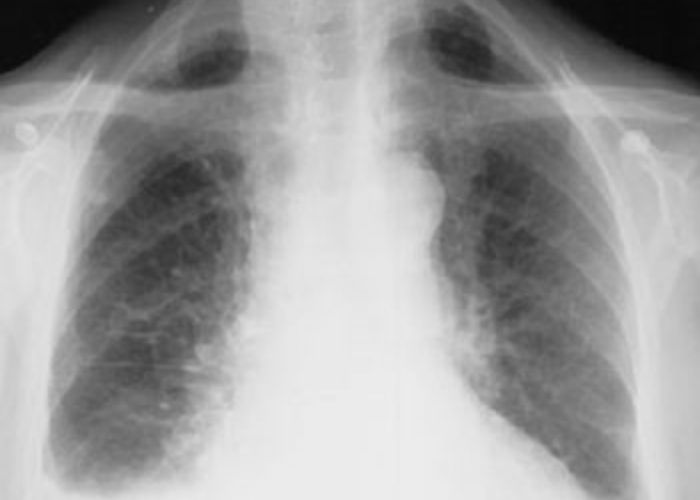

Akciğer Grafisi

Toraks BT de mezotelyomaya bağlı sıvı, nodüller veya kalınlaşmanın tespit edilmesi tanı için yeterli değildir ve mutlaka Plevradan biyopsi alınmalıdır.